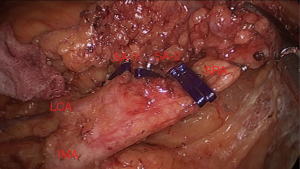

At the same time, we should dissect the lymph nodes along IMA, vein and their branch and preserved the left colic artery. After branching the left colic artery of IMA, we ligated the IMA and IMV (Figures 4,5).

Curative resection of rectal cancer included “high tie” and “low tie” of the IMA. “Low tie” included preservation of the LCA and lymph nodes dissection over the root of IMA (Figure 8). But it was controversial whether a high or low ligation of the IMA was superior. Some experts believed that there were no significant differences in the complication rate, operative time, the amount of blood loss, the number of days and OS and RFS rates between “low tie” and “high tie” with LND (9). But some scholars thought high tie may increase anastomotic leakage, because it reduced intestinal blood supply (10).